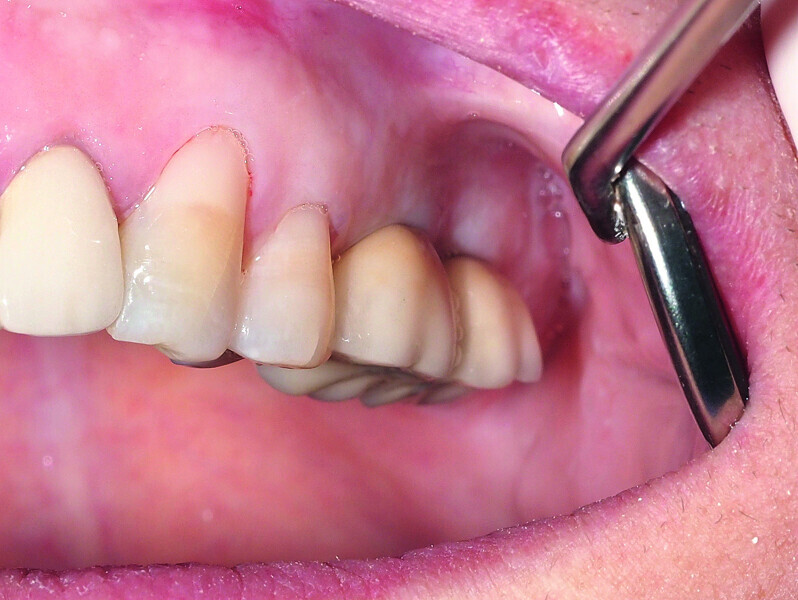

Fig. 14: Preoperative intraoral finding in the atrophic posterior mandible.

Fig. 15: Combination of full- and partial-thickness flap elevation.